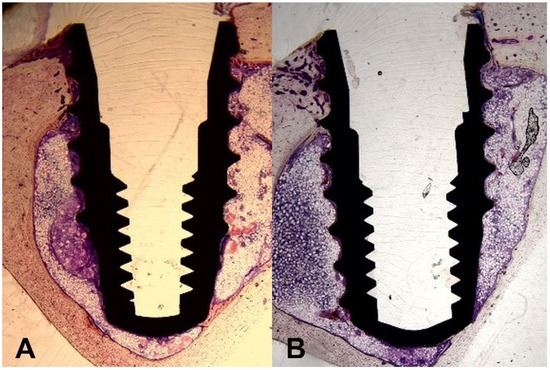

3.4. Comparison of Histological Results